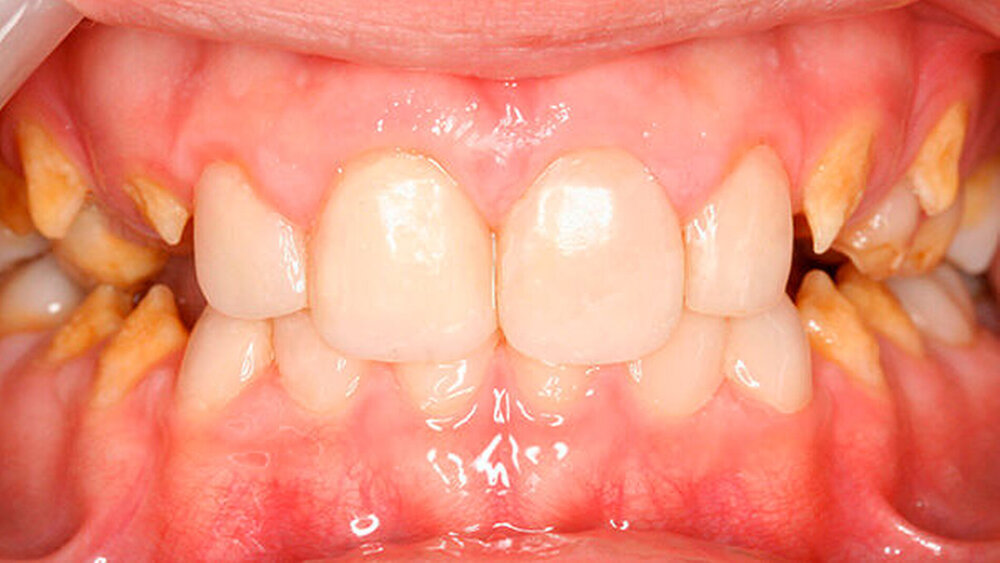

a) Dentinogenesis imperfecta. Da alle Zähne betroffen sind, ist von einer genetisch bedingten Fehlbildung auszugehen. Die Zähne der Patientin weisen zudem eine veränderte Farbe auf. Darüber hinaus sind Abplatzungen des Schmelzes vorzufinden. Trotzdem liegt keine Dentinogenesis imperfecta vor. Die Abplatzungen sind größtenteils geringfügig und zunächst oberflächlich, das heißt nicht unmittelbar bis zum Dentin. Die Farbänderung der Zähne entspricht nicht dem klassischen Bild einer Dentinogenesis imperfecta (siehe auch Abbildungen 3 und 4).

Zudem kann es immer wieder zu Abplatzungen des verbliebenen Schmelzes kommen, so dass der entsprechende Zahn eine neue Restauration benötigt, oder die schon vorhandene ausgedehnt werden muss (siehe auch Abbildungen 1 bis 3) [Crawford et al., 2007].